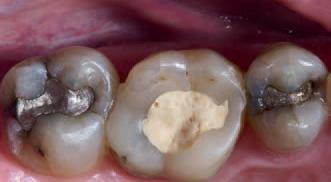

Clinical signs and symptoms

No teeth were tender to percussion. Tooth 26 reacted strongly to cold testing while the other teeth reacted normally. Tooth 26 tested positive to biting on damp gauze but the sensation did not linger. Both tooth 27 and 25 were negative to the bite test. The composite resin restoration in tooth 26 was removed under rubber dam and crack lines could be seen under the restoration (Fig. 1), with the most obvious running from the lingual to the centre of the tooth, and another from the mesiobuccal to the centre. A number of other minor cracks were visible, including one that ran under the buccal cusps (Fig. 1).

In 2024, the patient presented again with pain in tooth 26. He reported the tooth was very sensitive to cold, with the pain lasting several minutes. He also reported that the tooth had ached spontaneously at times. On examination, the tooth reacted very strongly to cold, which lasted for almost one minute. The tooth was also slightly tender to percussion. The composite resin restoration appeared sound (Fig. 2). A PA radiograph (Fig. 3) revealed no PARL, but the pulp chamber was reduced in size when compared to a previous bite-wing radiograph.

Procedure and treatment

Using local anaesthetic and rubber dam isolation, access was obtained through the composite resin restoration. While the cracks were visible, they appeared similar to the image from 2018 (Fig. 4). The roof of the pulp chamber was removed and vital tissue was found, which did not appear to be heavily inflamed (Fig. 5). A pulp stone was also present (Fig. 6). Removing this revealed bleeding pulp tissue at the opening of the root canals. A cotton pellet soaked in NaOCl was placed on the pulp tissue at the opening of the root canal and after five minutes the bleeding had ceased (Figs. 7 and 8).

As the plan was to restore the tooth with a full- coverage indirect restoration, the entire pulp cavity was filled with Biodentinee™ with the Bio-Bulk Fill technique. (Fig. 9).

The patient returned after twelve weeks and reported that the tooth had been asymptomatic (Fig. 10). At this appointment, a preparation for a ¾ crown was performed (Fig. 11). The Biodentinee™ was left in situ, cut back and used as a core for the restoration. A PVS impression was recorded, and a BISAcrylic temporary crown cemented with provisional cement (Fig. 12).

Three weeks later, a monolithic zirconia crown (Fig. 13) was bonded onto the tooth (Fig. 14). The tooth will be monitored and a review radiograph taken after six months.

Fig. 2: Pre-op composite resin restoration, 2024.

Fig. 10: Tooth at 12-week review.

Fig. 9: Cavity filled with Biodentinee™.

Discussion

This case highlights a number of elements of pulpotomies in teeth with cracks. Firstly, many teeth with deep cracks have a long-standing mild pulpitis, to which the pulp has responded by producing reparative dentinee that often appears in the form of a pulp calcification. The operator must be careful when performing vital pulp therapy on these teeth as it is often difficult to differentiate the pulp calcification from the floor of the pulp chamber.

Any pulp calcifications must be removed before assessing the condition of the radicular pulp tissue.

Secondly, in teeth with pulp symptoms resulting from cracks, it is best to perform a coronal pulpotomy. This allows the floor of the pulp chamber to be examined for any extension of the crack across the floor, which would greatly reduce the prognosis for the tooth.

Conclusion

The ability to use Biodentinee™ in the Bio-Bulk Fill technique has a number of advantages in cases like the above.

The initial vital pulp therapy appointment can be shortened by completely filling the cavity and using the Biodentinee™ as a permanent dentine replacement and an interim enamel replacement. The fact that the material can be left for up to six months allows time to assess the success of the procedure before committing to the final indirect restoration. The strength of Biodentinee™ means there is no requirement to place a separate core material.